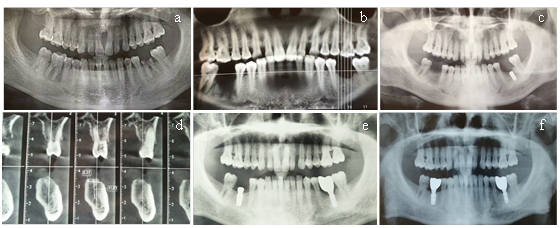

A 48-year-old male patient settled in the plateau area, with a chief complaint of implant denture restoration. The maxillary right lateral incisor of the patient was removed due to periodontitis. (Health status: smoking for 21 years, fasting blood glucose: 7.2mmol/L). Surgical approach: we made a midline incision on the edentulous alveolar crest, adding a vertical loose incision. Moreover, the full thick mucoperiosteum flap was developed. We placed an Osstem implant (3.3*10mm) after flap opened. The buccal bone defect was surgically treated by placing bone scraps and bone substitutes (Bio-Oss®) and covered with a resorbable collagen membrane (Bio-Gide®). Double-layer membrane technique was used to ensure longer barrier function (Bosshard and Schenk, 2010). CBCT showed preoperative and postoperative results (Figure 1a) (Figure 1b). Clinical photographs of preoperative and of 6 months after the operation (Figure 1c) (Figure 1d).

Figure 1 (a) CBCT of preoperation. (b) CBCT of postoperation. (c) Clinical photograph of preoperation. (d) Clinical photograph of 6 months after the operation.